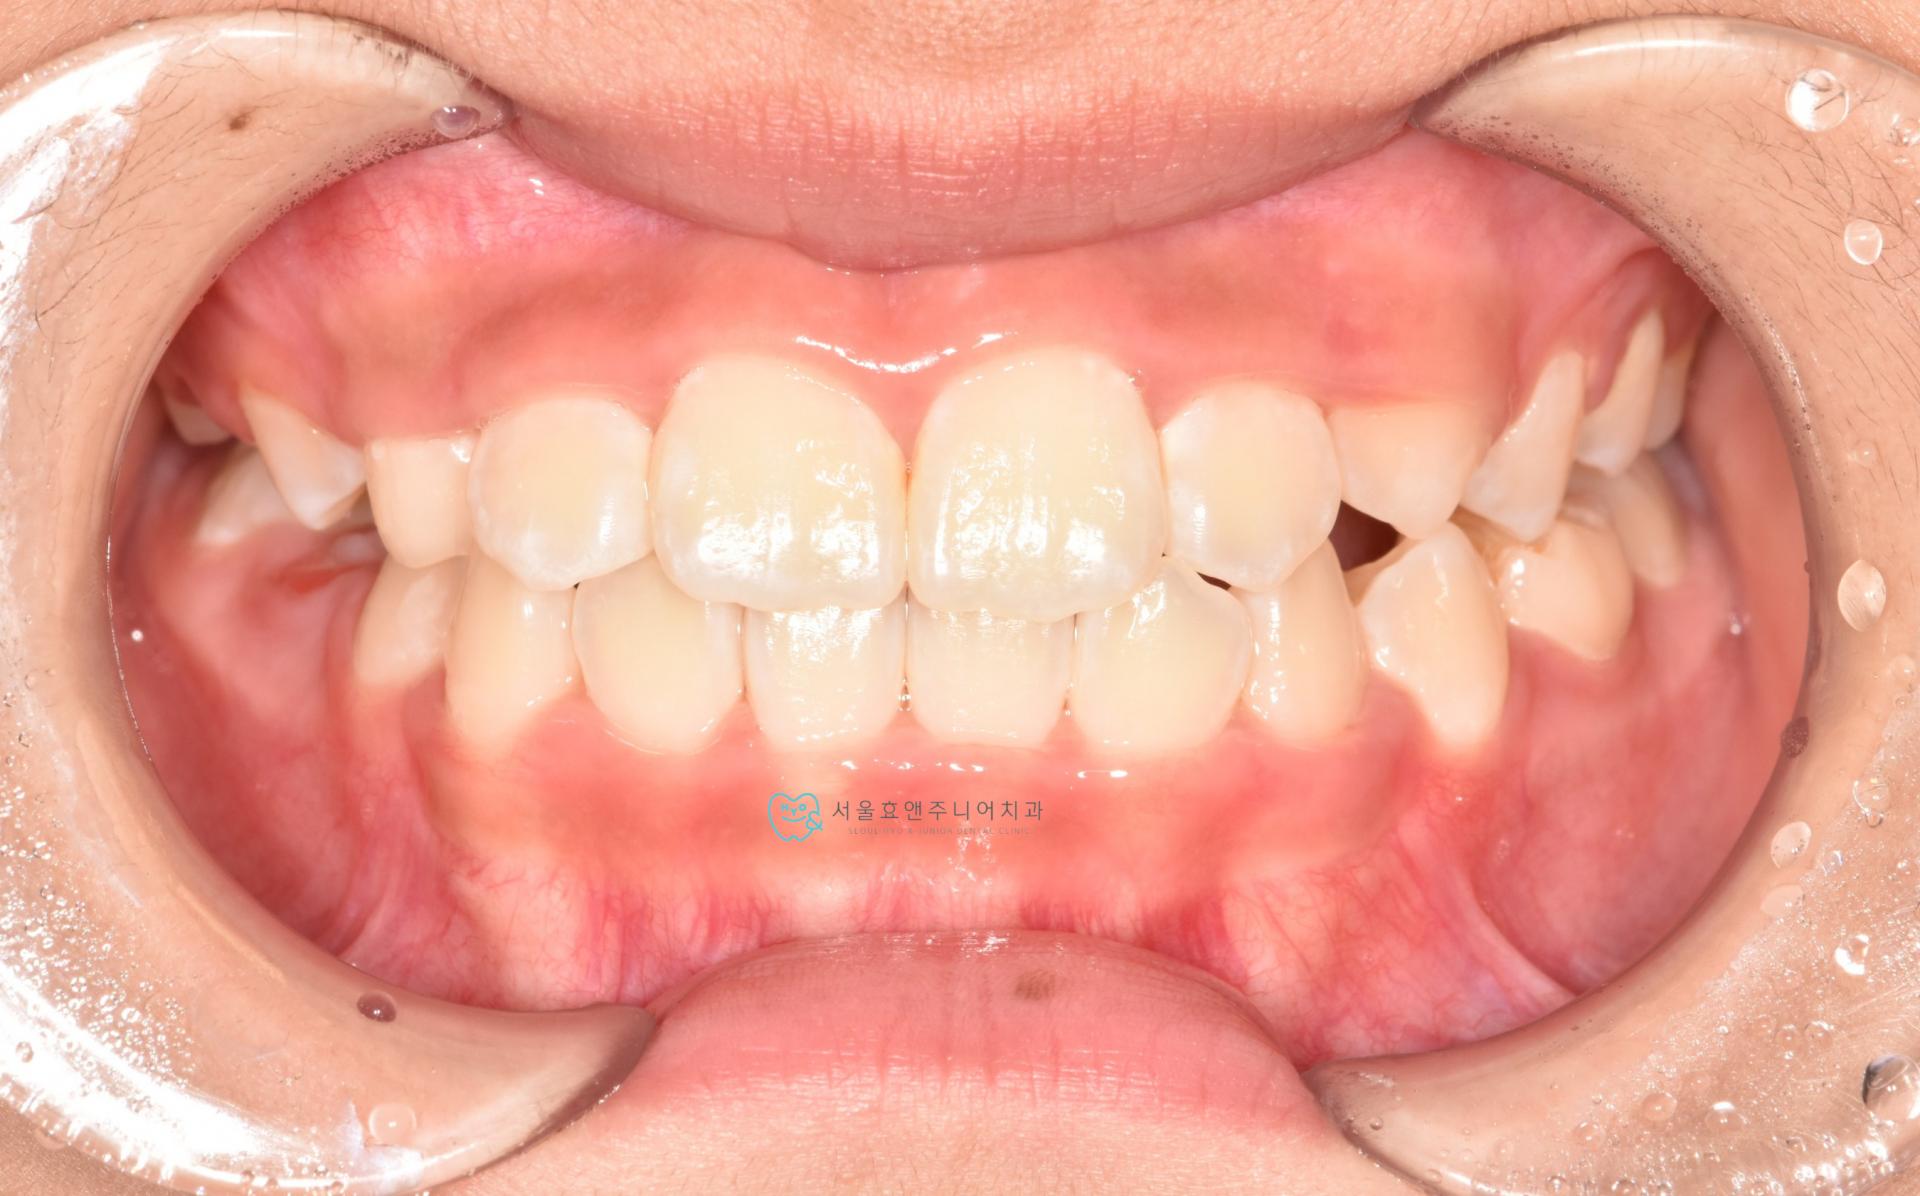

너무 예쁜 10세 11개월의 여자친구인데 반대교합이 있네요.

초진사진입니다. 앞니의 반대교합이 보입니다.

잘 때만 마우스피스형태로 물고 자는 프리올소를 사용하여 반대교합을 수정하였습니다.